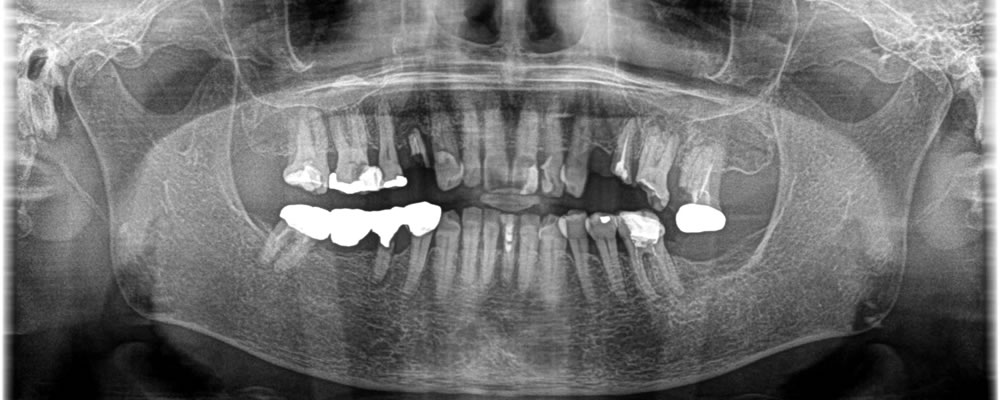

保存不可能な歯を抜歯後にインプラントで治療した症例

こちらはの患者さまは、当院にてインプラント治療を行った方のご紹介で歯がない部位や抜歯が必要な部位にインプラントを入れたいとのことで来院されました。

歯医者がかなり久々とのことで、むし歯により歯が根本から折れてしまった部位や、むし歯が大きく感染をおこしてしまい残すことができない歯を抜歯し、インプラントを埋入しました。